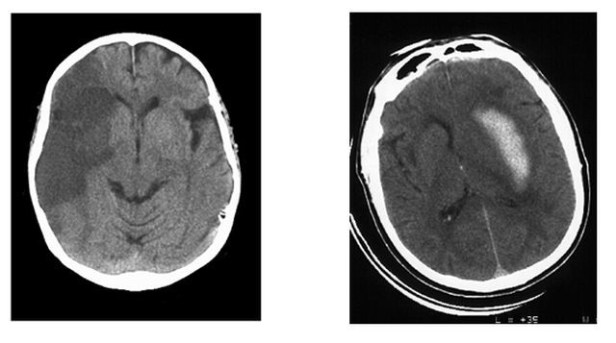

La función del TAC en la Ambulancia consiste en diagnosticar la causa del accidente cerebrovascular:

Si es debido a un coágulo de sangre (accidente cerebrovascular isquémico), tienen una mejor probabilidad de sobrevivir que aquellas que tienen un accidente cerebrovascular si es debido a sangrado en el cerebro (accidente cerebrovascular hemorrágico, debido a la ruptura de un vaso sanguíneo).

– Un estudio de TC cerebral, para clasificar si el ACV es isquémico o hemorrágico.